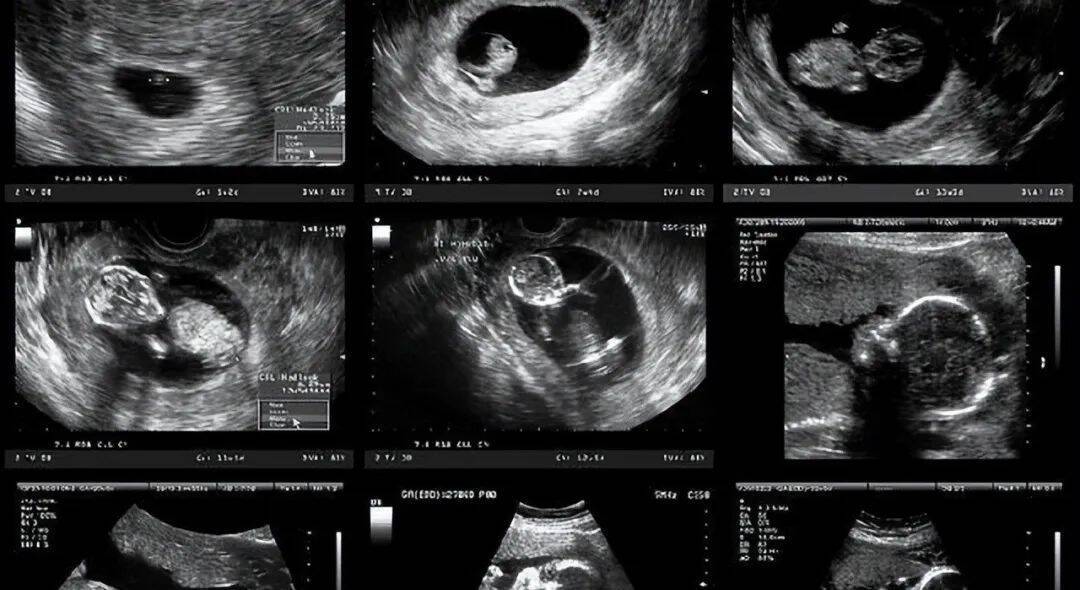

在怀孕40天左右的时候,孕妈身体会产生一系列的早孕反应,在怀孕六周左右时, 胎儿 有了心跳,医生通过B超影像可以测出胎儿的心脏活动。在之后的一周,小胎宝的四肢会慢慢成形,随后逐渐发育成成型人体的模样。

在怀孕12周后,胎儿的体重增长到20克,通过B超影像,医生可以清晰地看出胎宝的各个身体部位,其中,头部体积最大最为明显。此时医生也可以通过听诊仪听到胎儿的胎心,进而更好地确定胎儿的发育状态。

在怀孕6到8周时,此时孕妇所做的孕检项目主要是孕酮以及B超检查。如果在孕检时,医生发现孕妇体内孕酮含量增加出现异常,那么很有可能会判断其有先兆流产、胎停等情况发生了。而B超检查可以帮助医生确定孕妇是否存在宫外孕、多胎妊娠等情况。

在怀孕11到13周时,医生会要求孕妇进行NT检查。通过这种孕期检查可以排除胎儿畸形。